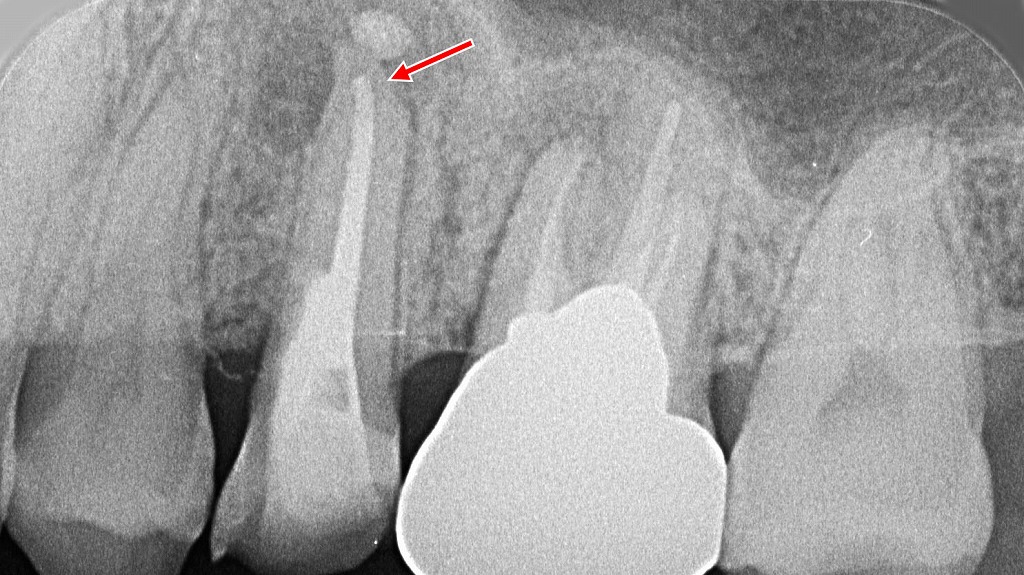

レントゲン画像から学ぶ

この写真は、根っこの先端に歯根嚢胞を形成したレントゲン画像です。矢印の部分にX線透過像(黒く映る部分)が認められ、ここに膿が溜まっています。

歯根嚢胞ができる原因は、根管治療がうまくいかず、歯根の中で細菌が繁殖するためです。歯根の形態が複雑になるほど、根管治療の難易度は上がります。

このように歯根嚢胞ができた場合には、再度根管治療をやり直す必要があります。それでもうまくいかない場合には、抜歯するか、外科的に歯根嚢胞を摘出する手術が必要になります。